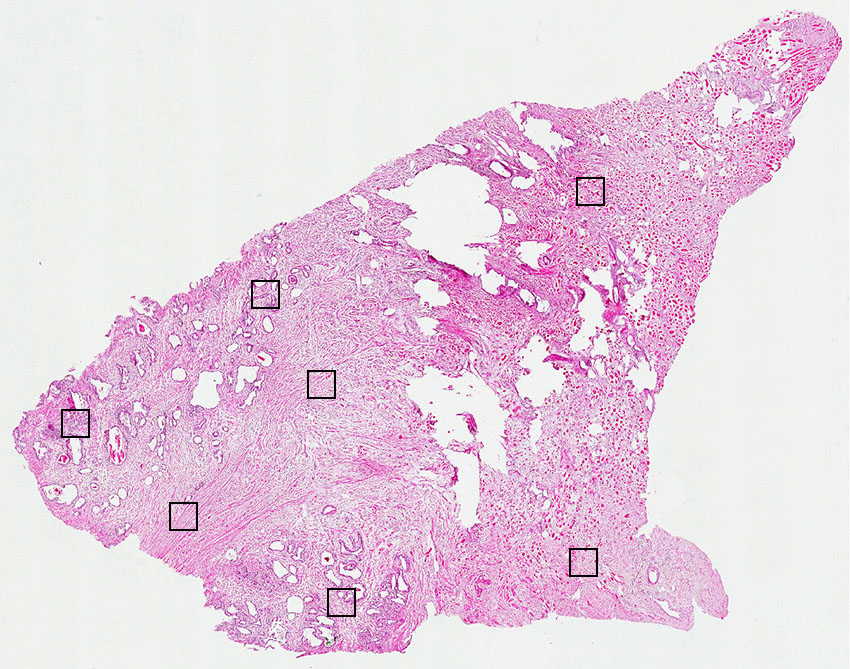

Cell types%

Glandular cells:

30

Smooth muscle cells:

55

Skeletal muscle cells:

5

Other cell types:

10